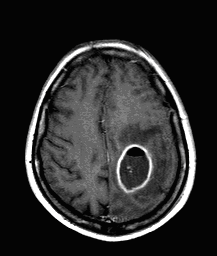

Metastases:

The most common primary tumors that metastasize to the brain are: bronchus carcinoma, breast cancer and renal cancer. A so called early metastasis is especially typical for bronchus carcinoma, when the primary broncus carcinoma is still unknown.

Small metastases can produce very extensive edemas. Multiplicity is common. Due to the consequential blood-brain barrier disorders their contrast enhancement is very intense.